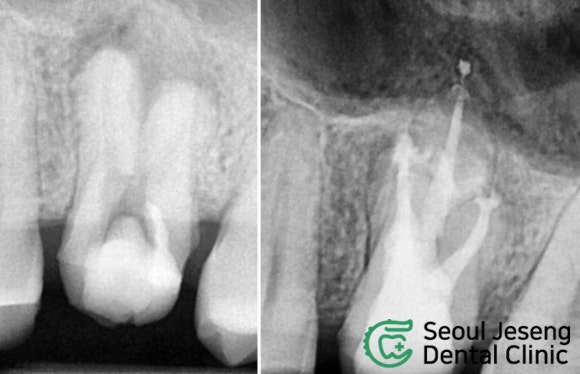

치료 전과 비교해볼까요?

환자분과 함께 치료 전 CT와

한 달 반 경과 후 찍은 CT를 비교해봅니다.

엑스레이 상 염증은 모두 사라졌고,

환자분도 편안해 하십니다.

이제 마무리할 때가 된 것 같습니다.

치료 전 후 엑스레이 사진입니다.

뿌리 끝까지 알차게 충전이 되었습니다.